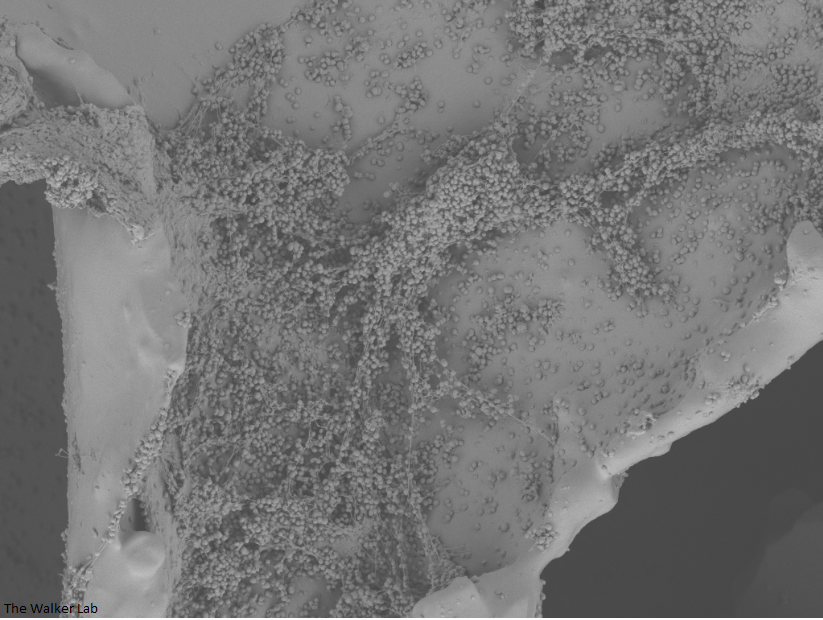

SEM Images of Mouse Catheters

Silicone urinary catheters have smooth surfaces, while latex urinary catheter surfaces are rough. Regardless of the catheter material, deposition of host inflammatory factors alters the surface and facilitates infection by atypical pathogens.

Host Immune Cells and Glycoproteins

Urinary catheters render people susceptible to atypical uropathogens. We use the atypical uropathogen, methicillin-resistant Staphylococcus aureus (MRSA), to study the catheter-host-pathogen interactions that facilitate disease.

The host inflammation response to the catheter recruits immune cells and wound healing proteins which are deposited on the catheter surface. Atypical pathogens can use these host factors to adhere to the catheter's large surface and create biofilm. Colonization of catheters occurs quicker than expected and develops even in the presence of prophylactic antibiotic therapy. MRSA is just one of the uropathogens that can attach to the altered urinary catheter surface. One host factor deposited on the catheter surface is fibrinogen. We recently discovered that MRSA binds fibrinogen to attach to the catheter surface and form biofilm, which increases antibiotic recalcitrance. Our future studies aim to develop new non-antibiotic strategies that interfere with those interactions to prevent or treat CAUTIs.